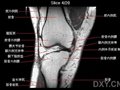

自行车常见运动伤害——抽筋、